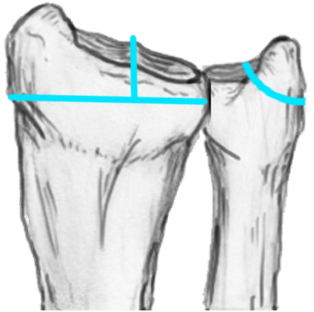

Radial angles

| Volar tilt mean 11° | Radial inclination mean 22° | Radius mean 11 mm longer than ulna |